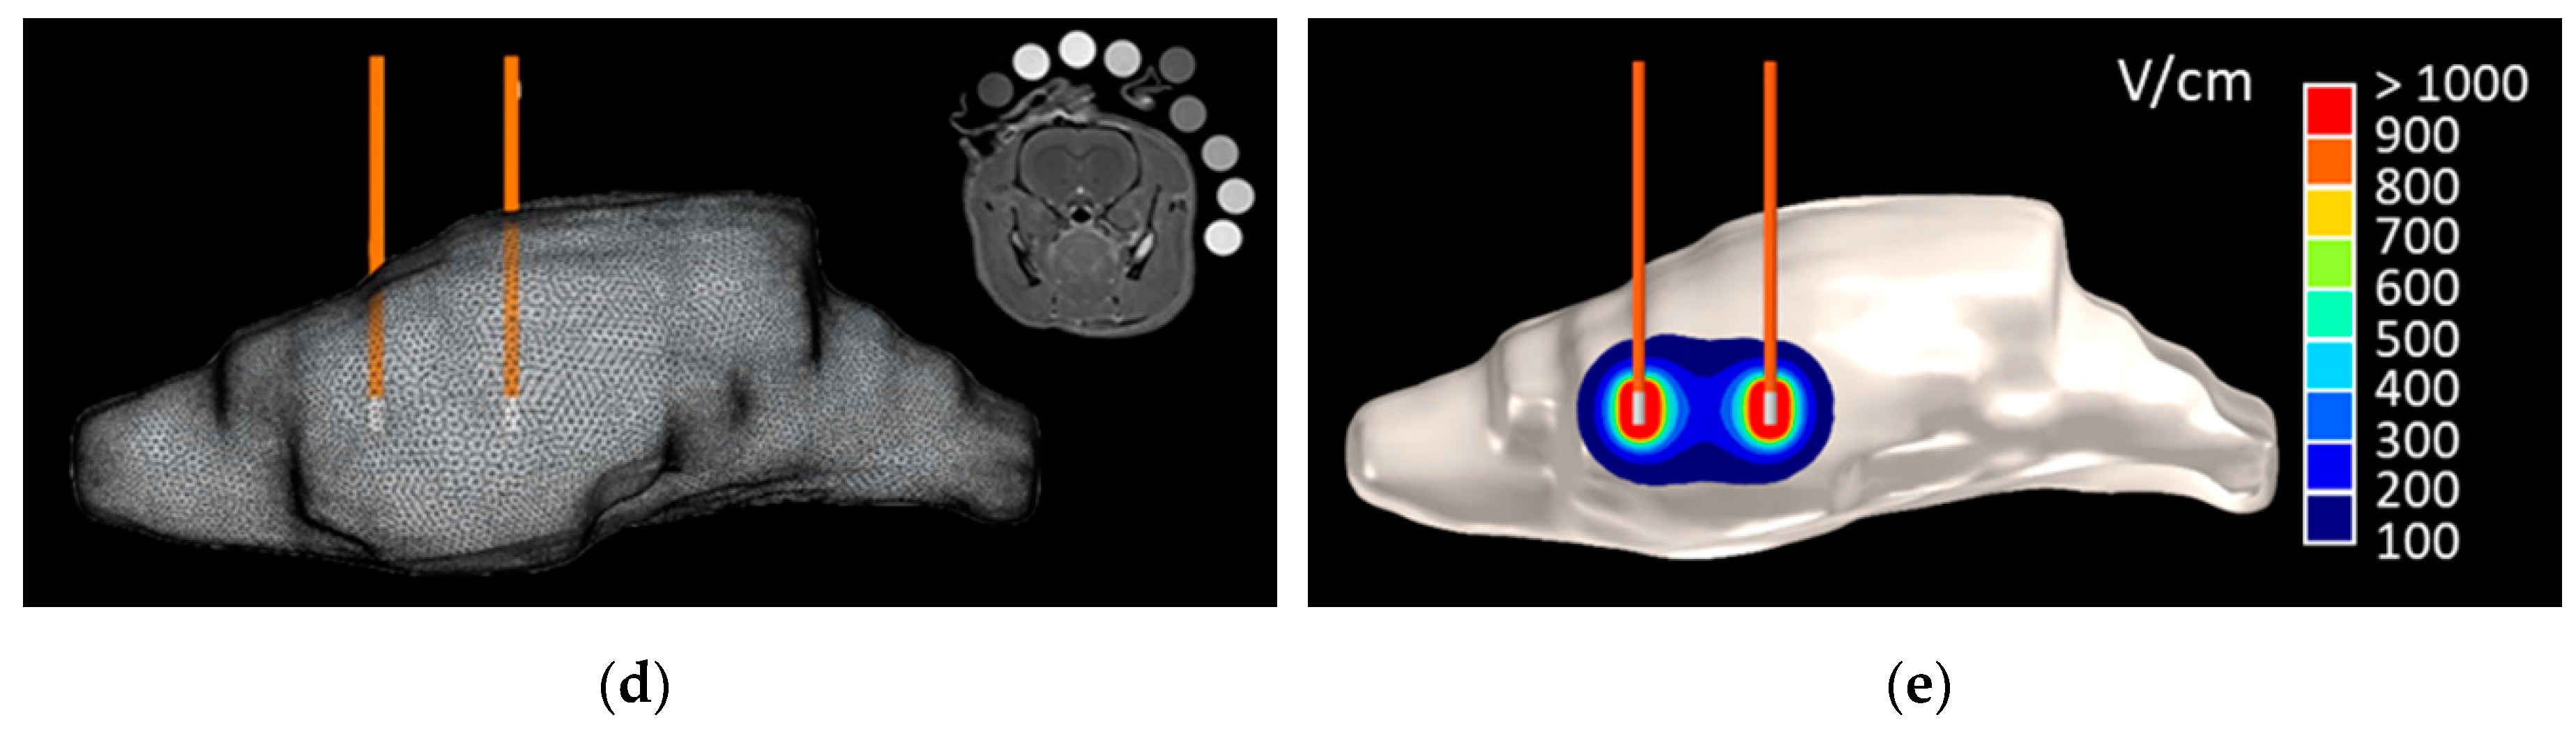

2.2. Numerical BBBD Analysis

4.6. Numerical Determination of BBBD Temporal Thresholds